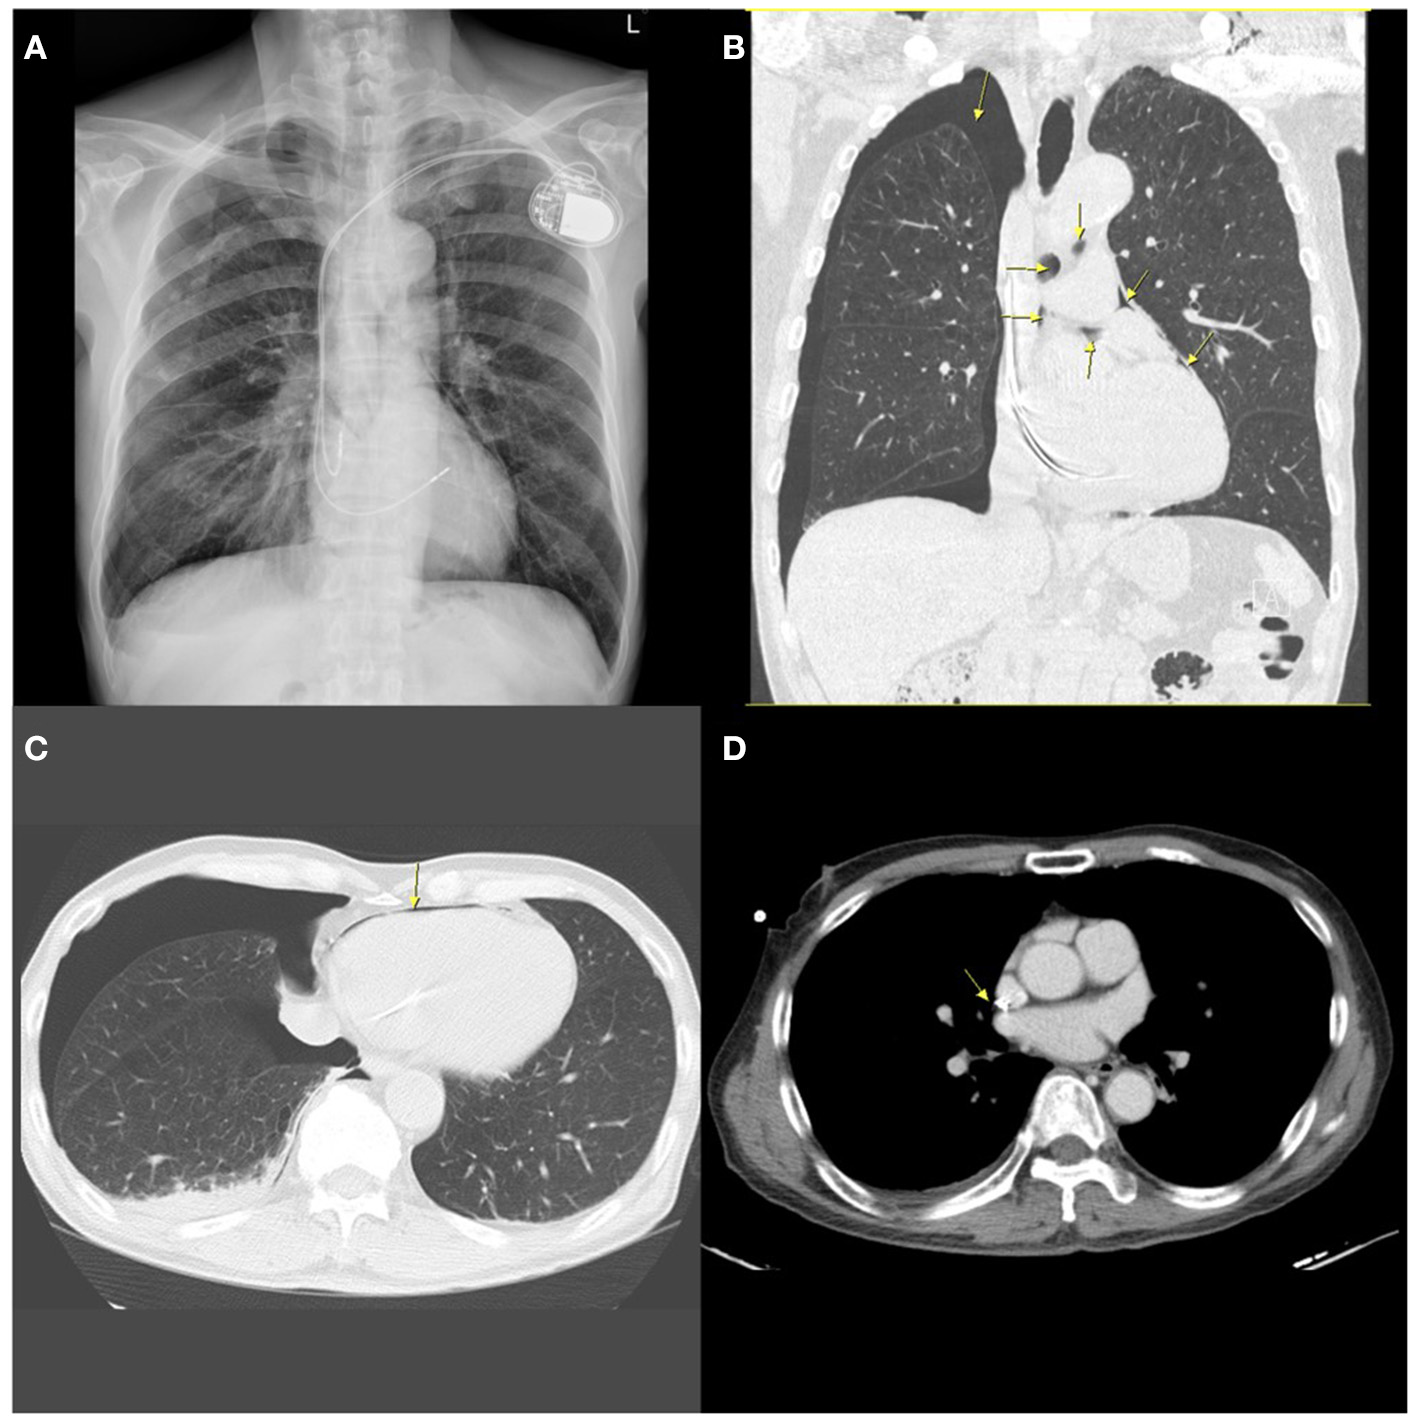

The implantation procedure was completed uneventfully. Two h after the implantation, the chest radiographs revealed acceptable lead positions and no evidence of pneumothorax. There was no pericardial effusion on echocardiography. About 5 h after the procedure, the patient suddenly reported dyspnea, severe headache, neck stiffness, and shoulder pain. A chest X-ray (CXR) revealed a 3.5 cm right-sided apical pneumothorax as well as small amounts of gas as linear or curvilinear lucencies in the mediastinum, indicating pneumomediastinum. Non-contrast computed tomography (CT) of the chest showed bilateral emphysema, right-sided pneumothorax with pneumopericardium and pneumomediastinum, a small right-sided pleural effusion, and the atrial lead crossing the cardiac contour, suggesting lead perforation through the pericardium and directly into the pleural cavity (Figure 1).

Figure 1

A chest radiograph performed 5 h after implantation showing contralateral pneumothorax, pneumopericardium, and pneumomediastinum. (A) Posterior-anterior (PA) chest X-ray demonstrating contralateral pneumothorax and mild pneumomediastinum. (B) Coronal chest non-contrast computed tomography (CT) scan image showing right-sided pneumothorax, pneumomediastinum, and pneumopericardium (arrows). (C) Horizontal CT image showing pneumopericardium (arrow) and pneumothorax. (D) Horizontal slices of CT scan suggesting possible extrusion of the atrial lead through the right atrium (arrow).